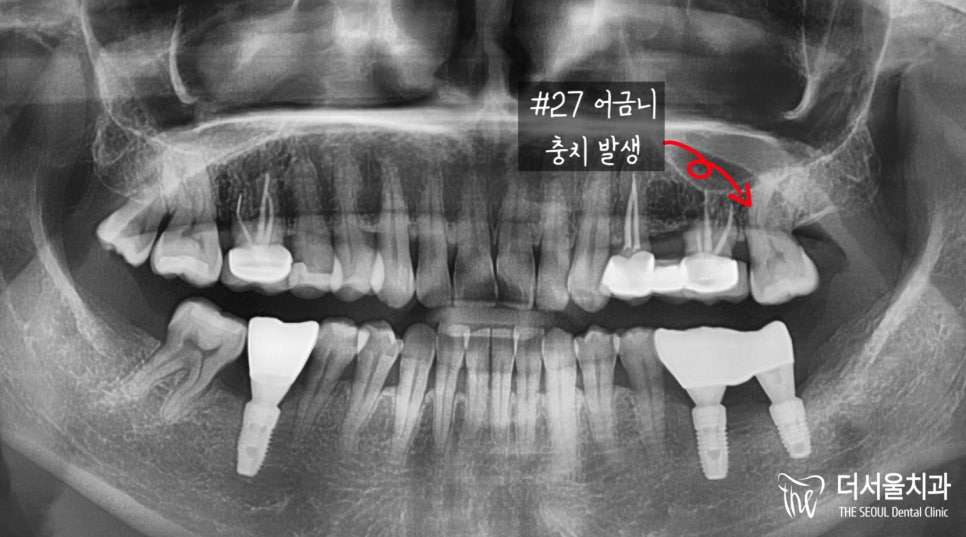

파노라마로 해당 어금니를 확인했을때,

충치가 생긴 것을 볼 수 있는데요.

확인이 힘든 여러분들께

잘 보여질 수 있도록 확대하여 보여드리겠습니다.

이미 치수까지 침투했기에

서둘러 신경치료를 진행해드려야 되었습니다.

그 후에 크라운 보철을 씌워줘야 되었구요.